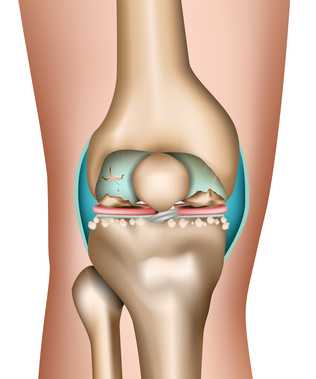

Артроз (износ) суставного хряща — это самое известное суставное заболевание. Одной из наиболее распространенных форм болезни является артроз коленного сустава - патология, являющаяся причиной хронической боли, а также ограниченности в движениях больного. На протяжении нескольких лет скользящая поверхность суставного хряща постепенно снашивается, в связи с чем медленно теряет свои исходные свойства. Так как у хрящевой ткани отсутствуют нервные окончания (ноцицепторы), травмы колена становятся ощутимы лишь тогда, когда дефект достигает костного слоя, находящегося под суставным хрящом.

Причины болезненного износа суставного хряща коленного сустава - это артрит, артроз, травмы с деформациями костей либо хрящевых структур, нарушение обмена веществ, а также подагра или гемохроматоз. © bilderzwerg @ fotolia

Хрящ играет очень важную роль, выступая в качестве подушки внутри сустава. Здоровые ткани хряща суставов являются гладкими, гибкими и безболезненными. Если хрящевые ткани повреждены, то этот ущерб, как правило, остается навсегда, суставы становятся болезненными, снижается их подвижность. Хрящ не может регенерироваться естественным путем внутри тела пациента. Через некоторое время за не имением "амортизатора" кости сустава начинают сталкиваться. Суставы воспаляются, подвижность уменьшается и в конце концов встает вопрос о имплантанте сустава. Этот болезненный процесс представляет собой необратимый процесс развития остеоартрита. Необратимость процесса повреждения хряща воспринималась пациентами и врачами во всем мире как факт жизни - до сих пор.